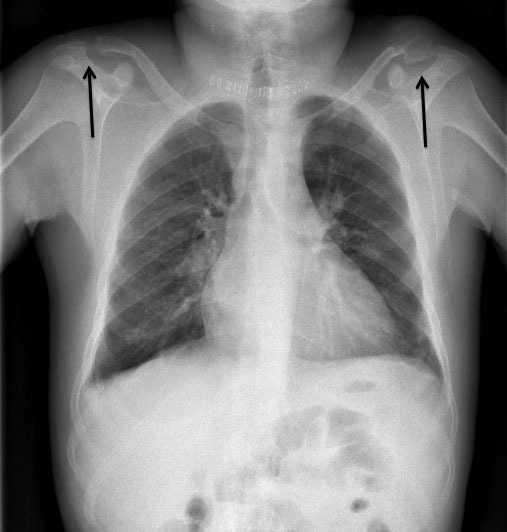

Figura 3. Imagen de radiografía de tórax en la que se aprecian tumores pardos en ambas clavículas